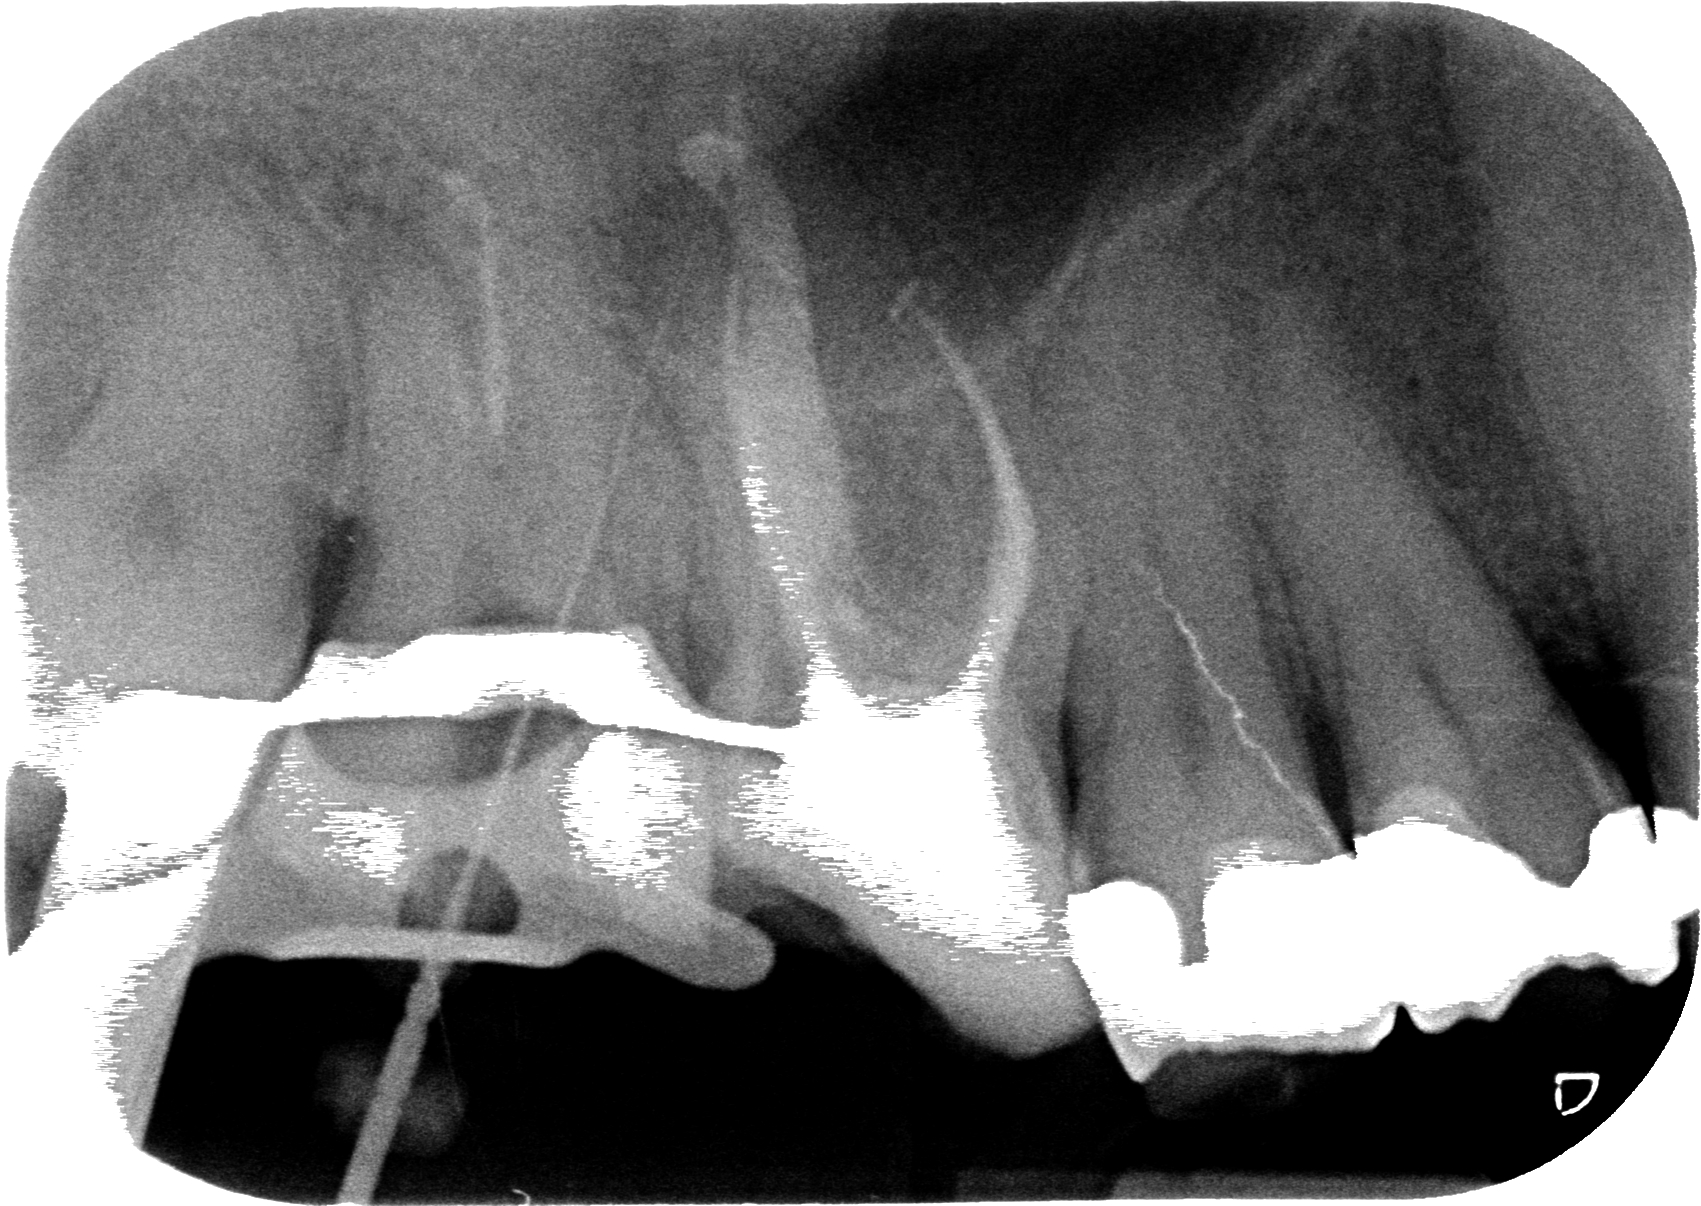

“Ok, come temevo è molto probabile che siamo finiti fuori strada, facciamo una piccola lastra di verifica per capire dove siamo andati…”

Ed ecco la rx.

A questo punto il paziente non si preoccupa perchè si è verificato esattamente quello che avevi previsto e capisce che la situazione è difficile ma sai cosa stai facendo.

Sapendo che sono andato dritto mesialmente mi dimentico di quella via e con gli ultrasuoni mi creo un piccolo pozzetto in direzione distale. Faccio un paio di volte qualche tentativo con ultrasuoni e poi file, ma nulla. Ok, questo è il momento di capirci qualcosa in più perchè non possiamo rischiare di trasformare la radice in un groviera.